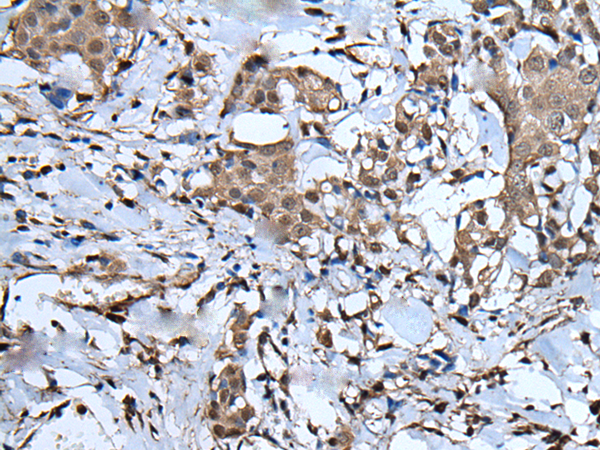

IHC positive control: |

Human liver cancer and human breast cancer |

IHC Recommend dilution: |

40-200 |